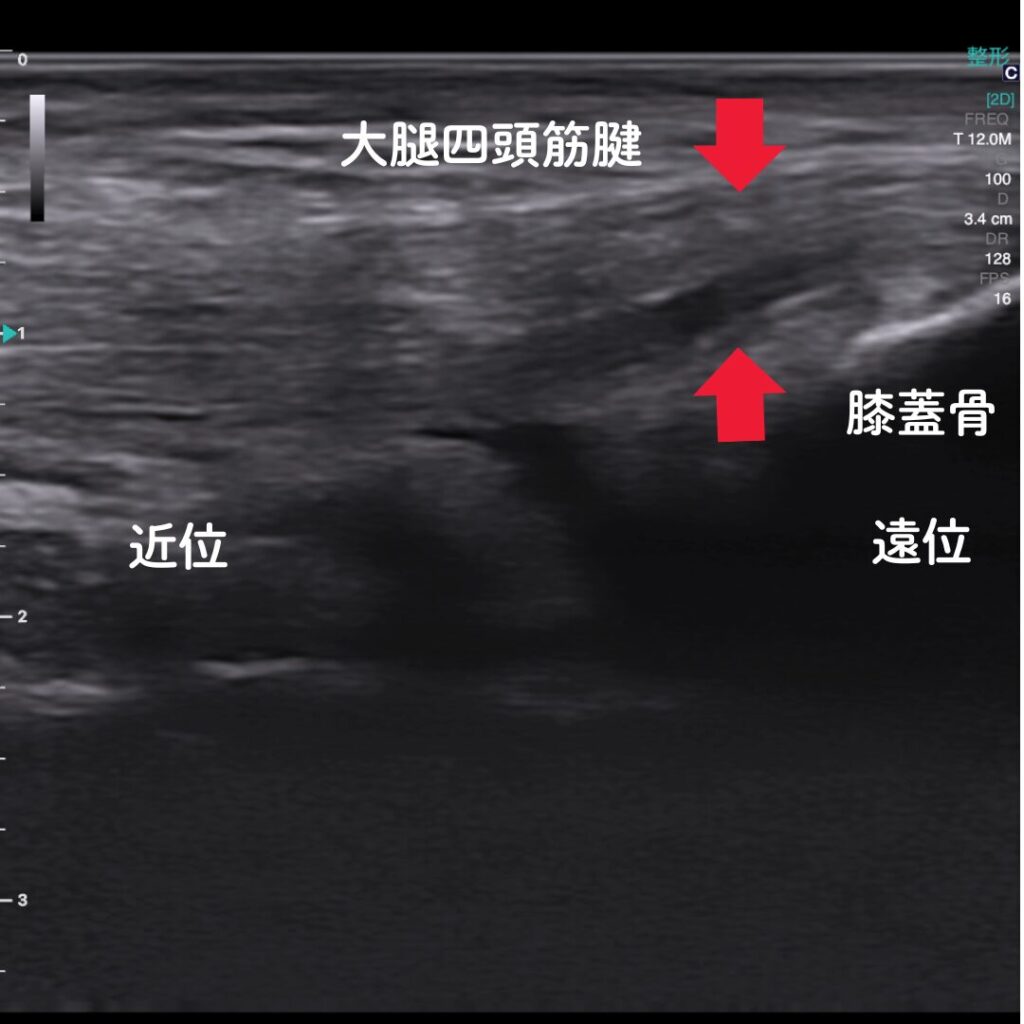

🔶エコー(超音波観察装置)で原因を“見える化”

エコー観察により、膝蓋腱の炎症や損傷の程度をリアルタイムで確認できます。

レントゲンでは写らない腱や軟部組織の状態を可視化し、痛みの原因を正確に特定します。

また腱付着部の骨異常も観察可能。